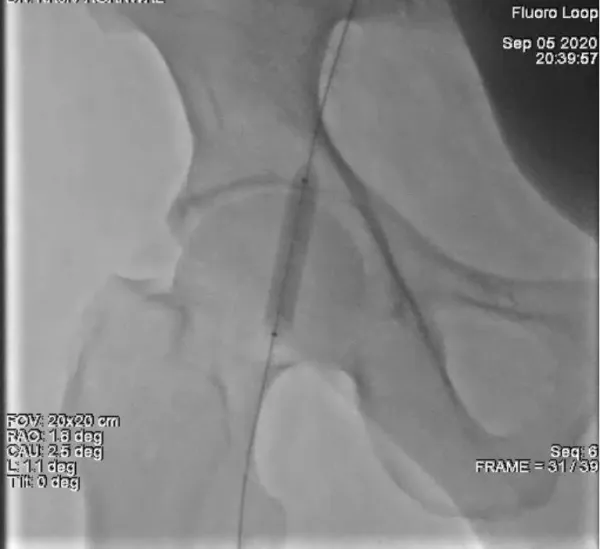

Through the Judkins right (JR) 6 catheter, a 0.035 inch magic torque guide wire (260 cm) [Boston Scientific] was passed across the common femoral artery into the distal right superficial femoral artery. The JR6 catheter was then withdrawn leaving the wire in the distal superficial femoral artery. A 8 x 40 Armada 35 PTA Balloon (Abbott Vascular) was inserted over the magic torque guide wire and balloon tamponade was performed over the leaking site for a total of 15 min at a inflation pressure of 4 atm (Figure 3). Total two inflations were done with a gap of 5 minute in between.

Download Image

Figure 3: Demonstrates Balloon tamponade of the leaking right common femoral artery via left femoral approach.